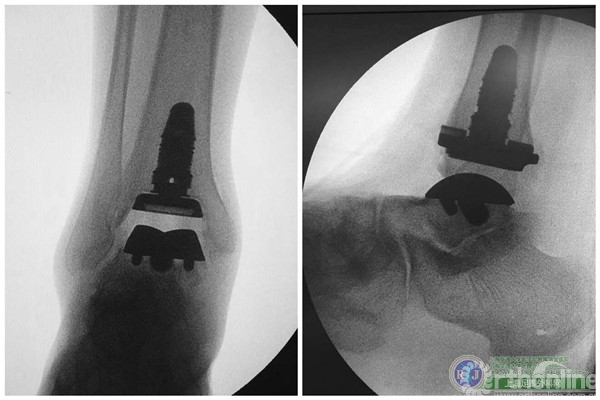

上海瑞金医院骨科足踝外科团队于2015年10月28日上午成功对该患者实施了第三代全踝关节假体(INBONE® II. Wright.)置换手术,手术过程非常顺利。手术中首先清理踝关节内外侧炎性组织及骨赘,将患足置于专门的定制支架中,在透视下反复调整足踝及导针位置,力求最高精确度。在截骨导板的定位下进行踝关节胫骨及距骨的截骨,试样假体大小,置入合适匹配的踝关节假体及垫片完成全踝关节假体的置换,全程手术时间90分钟。完成的全踝关节假体置换位置精确,假体设计稳定牢固,踝关节内外侧软组织平衡,达到了预期的效果。术后患者恢复良好,手术取得圆满成功。患者在休养五周左右以后可以下地行走,去除踝关节炎疼痛畸形的同时能够保留踝关节的活动度,为生活和工作提供极大便利。

国内首例INBONE全踝关节假体置换手术的成功完成开启了中国骨科手术治疗终末期踝关节炎的新篇章,这为千千万万饱受踝关节炎困扰的患者带来了福音。